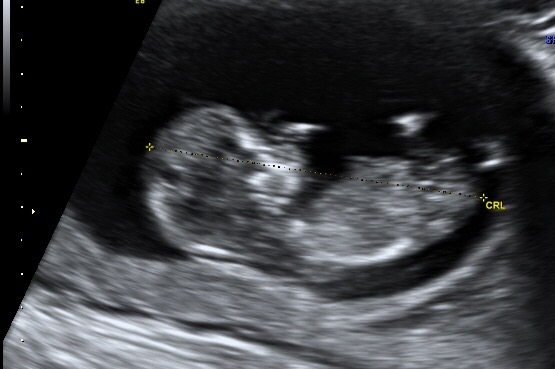

• 9wk 4d. Baby stretched out for us! Just Hangin out :)